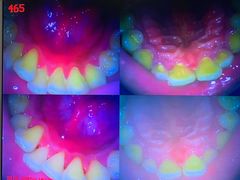

• 土豆口腔(凤凰北总店)

• -土豆口腔(凤凰北总店)